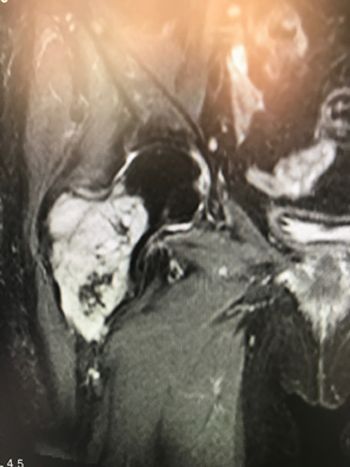

Se completa el estudio de con una resonancia (figura 2), en la cual se aprecia una lesión expansiva y de características agresivas. Se realiza biopsia guiada con radioscopia y es informada como Condrosarcoma de grado II. Dicho tumor solo tiene tratamiento quirúrgico. Tras ser valorado conjuntamente con el servicio de geriatría se decidió realizar el tratamiento estandarizado en estos casos que consistió en una cirugía agresiva con el objetivo de realizar una resección en bloque del tumor (foto 3) y sustitución del defecto creado por una megaprótesis tumoral cementada, (foto 4).